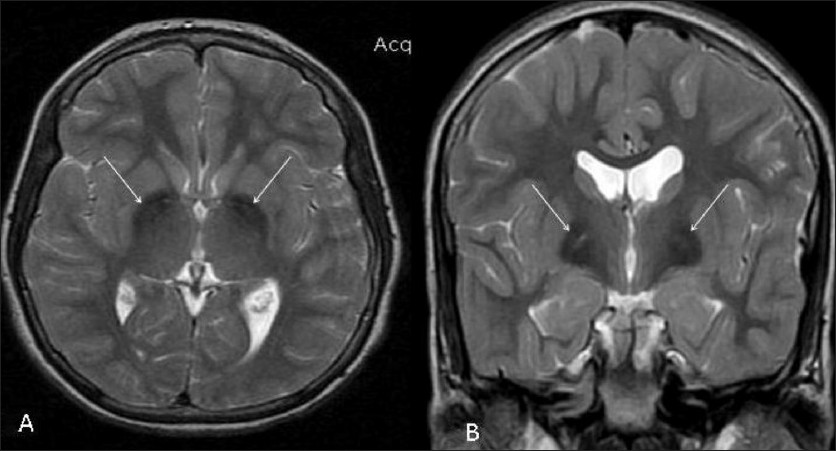

E' considerata una malattia genetica molto rara l'aceruloplasminemia, una patologia caratterizzata da un forte accumulo di ferro in alcuni organi del nostro organismo, tra i quali fegato e cervello. E' la conseguenza dell'assenza di ceruloplasmina, una glicoproteina fondamentale per trasportare il rame ma, soprattutto, per rimuovere il ferro dai tessuti grazie all'attività dell'enzima ferrossidasi. L'aceruloplasminemia si manifesta verso i 30 anni, quando i primi sintomi cominciano a comparire.

Il primo segnale di allarme legato all'aceruloplasminemia è certamente il diabete o il danno pancreatico conseguente all'accumulo di ferro nelle cellule beta responsabili della produzione di insulina. Se accompagnato da una degenerazione della retina può essere l'elemento che indica l'insorgere di questa rara malattia genetica, provocata, come sopra accennato, da mutazioni nel gene della ceruloplasmina e dunque da problematiche nel processo di metabolismo del ferro. Occorre sottolineare che questa patologia viene ereditata dai genitori, tramsettendosi ai figli solo nel caso di ereditarietà delle due copie alterate del gene da entrambe i genitori. Tra i sintomi che compaiono in ettà più avanzata, ovvero tra i 40 e i 50 anni, vi sono tremori, difficoltà ad articolare le parole, ed altri sintomi neurologici come la rigidità del movimento e anche la demenza.Come diagnosticare l'aceruloplasminemia

Non è facile fare una diagnosi accurata di questa malattia, considerando il fatto che in Europa le stime epidemiologiche parlano addirittura di meno di un caso su un milione. L'aceruloplasminemia si manifesta con maggiore frequenza in Giappone ma sempre in forma rara, con un caso registrato oggni 1-2 milioni di matrimoni tra non consanguinei; inoltre sia l'uomo che la donna vengono colpiti in egual misura. Inoltre, a differenza di quanto avviene con la malattia di Wilson, non si riscontrano apparenti difetti per quantro riguarda il metabolismo del rame; invece il danno è legato all'eccessivo accumulo di ferro nei tessuti ed oltre al fegato può essere localizzato anche nel pancreas e nel tessuto nervoso dando origine a forme di decadimento di cognitivo come la demenza.Cura e terapie da seguire